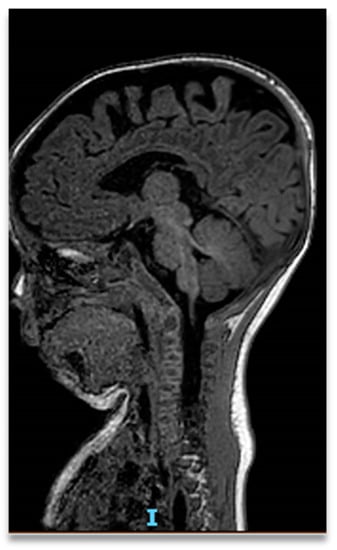

Cleft Palate and Aortic Dilatation as Clues for Loeys–Dietz Syndrome

2. Case Report